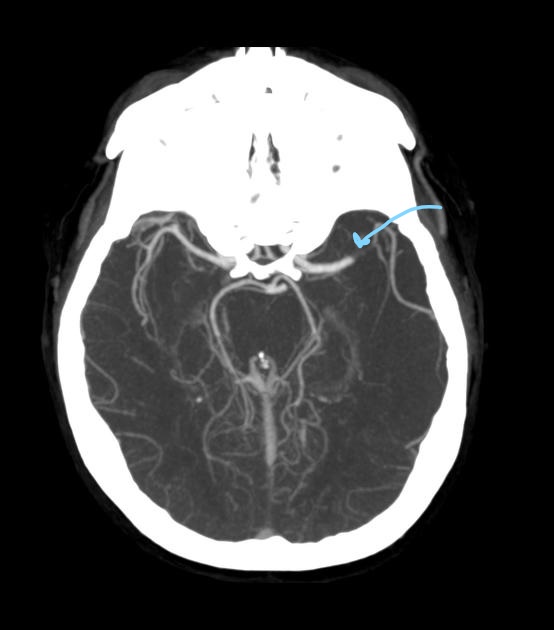

What is a Maximum Intensity Projection (MIP)?

A reconstruction technique that displays only high HU voxels to enhance visualization of contrast-filled vessels.

Why are MIPs essential for CTA interpretation?

They remove low-attenuation tissue and highlight vascular anatomy.

What plane best demonstrates the Circle of Willis?

Axial and coronal head MIPs.